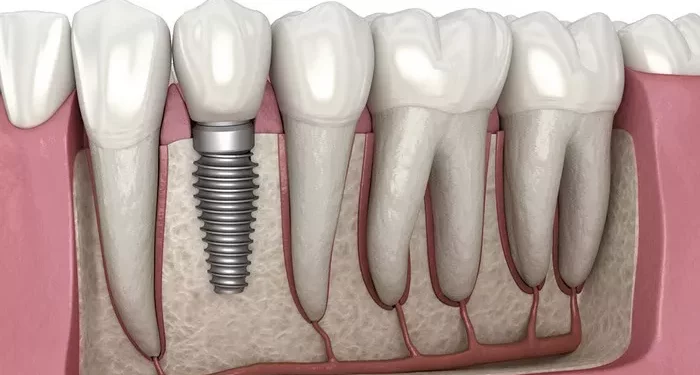

Full-mouth dental implants are designed to replace most or all missing teeth by anchoring fixed restorations to implants placed in the jawbone. According to current dental cost references, the total expense of full-mouth implant procedures varies depending on the number of implants needed, the type of full-arch restoration selected, and any additional procedures such as bone grafting, tooth extractions, or advanced imaging. Insurance coverage can also impact out-of-pocket costs, depending on policies related to implants, crowns, and annual or lifetime limits.

Implant evaluations at Advanced Smile Dentistry typically begin with three-dimensional imaging and clinical examinations to assess bone volume, anatomical considerations, and the type of restoration most suitable for each patient. These evaluations determine candidacy for full-mouth implant treatment and identify any additional planning steps required before surgery.